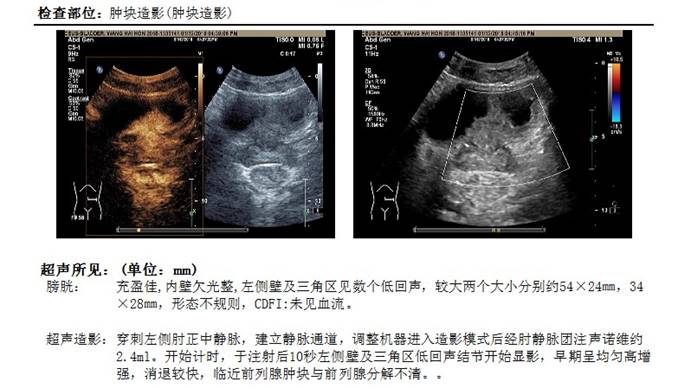

现病史:患者2018.1.12因“血尿半年余”至我院就诊,呈间断无痛性终末血尿,泌尿系超声提示:膀胱左侧壁及三角区低回声占位,超声造影:首先考虑膀胱癌,伴前列腺浸润可能(图1)。

图1 2018年1月12日超声肿块造影